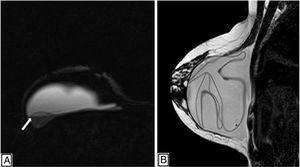

Breast magnetic resonance imaging. (A) Silicone-only sequences showing a posterior and external image with the same signal intensity as silicone as a result of intracapsular silicone gel bleed (white arrow). (B) Sagittal T2-weighted sequence with hypointense lines as a linguine sign in ICR.